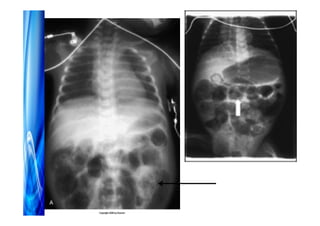

Enterocolite necrosante

Prematuridade

Nutrição enteral

Fatores patológicos

•Isquemia intestinal

•Agentes infecciosos

•Prática nutricional (inicio, volume de progressão,

tipo de leite, osmolalidade)